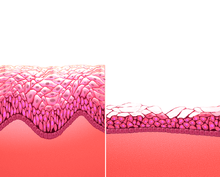

The epithelial covering of the cervix is continuous with the epithelial lining of the vagina. The vaginal mucosa is absent of glands. The vaginal epithelium consists of three rather arbitrary layers of cells[21] – superficial flat cells, intermediate cells and basal cells – and estrogen induces the intermediate and superficial cells to fill with glycogen. The superficial cells exfoliate continuously and basal cells replace them.[13][22][23] Under the influence of maternal estrogen, newborn females have a thick stratified squamous epithelium for two to four weeks after birth. After that, the epithelium remains thin with only a few layers of cells without glycogen until puberty, when the epithelium thickens and glycogen containing cells are formed again, under the influence of the girl's rising estrogen levels. Finally, the epithelium thins out during menopause onward and eventually ceases to contain glycogen, because of the lack of estrogen.[13][23][24] In abnormal circumstances, such as in pelvic organ prolapse, the vaginal epithelium may be exposed becoming dry and keratinized.[25]

Before and during ovulation, the mucus glands within the cervix secrete different variations of mucus, which provides an alkaline, fertile environment in the vaginal canal that is favorable to the survival of sperm.[32] As women age, vaginal lubrication decreases, which does not necessarily mean that a physical or psychological problem exists.[33] After menopause, the body produces less estrogen, which, unless compensated for with estrogen replacement therapy, causes the vaginal walls to thin out significantly.[13][23][34]